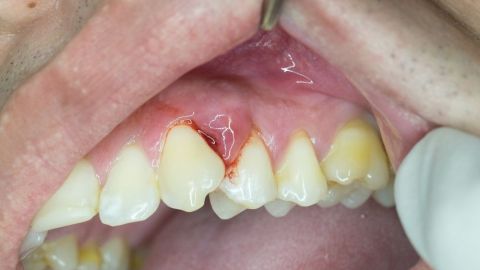

La enfermedad periodontal es una afección en las encías, que en su última etapa, puede disolver el hueso que mantiene a los dientes en su lugar.

El sarro, placa bacteriana entre los dientes, si se acumula demasiado se convierte en arenilla dura, llena de bacterias, que se esparce a la encía y la infecta. Esto se conoce como gingivitis, la forma más leve de la enfermedad periodontal.

Cuando este proceso avanza, se forman bolsas periodontales entre la encía y los dientes, que afectan al hueso maxilar, encargado de sujetar los dientes. Aquí ya se convierte en periodontitis leve, segunda etapa de la enfermedad.

Cabe destacar, que la encía también sufre cambios: se aleja de los dientes, creando una hendidura. Y si los dientes no se caen por sí mismo, de igual forma deben ser extraídos, por no tener cimiento para mantenerse.